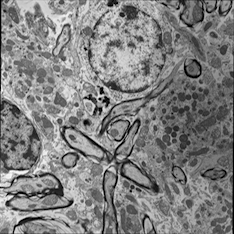

For image analogies based image registration, I have corresponding TEM/Confocal Microscopic image pairs of mouse brains with corresponding regions highlighted by a box. Using the correlative microscopy technique on the mouse brain, I want to localize specific brain regions associated with Pelizaeus-Merzbacher Disease (PMD) and do quantitative assessment of hypomyelination and demyelination in mice. PMD is one of a group of genetic disorders characterized by progressive degeneration of the white matter of the brain affecting the myelin sheath, the fatty covering that acts as an insulator on nerve fibers in the central nervous system.

The confocal microscopy images are multichannel color images in our test dataset. The blue channel is based on the blue stain DAPI (a fluorescent stain) which stains the DNA of the cell nucleus and corresponds to dark regions within the nuclei in the TEM. The green channel is based on the stains of the myelin sheats, visible as dark black layers covering the neurons in the TEM images. The red channel is not explicitly stained for and is caused by the auto-fluorescent effect of lipofuscin. The confocal image with RGB channels and its corresponding TEM image are shown in Fig. 5.

Currently I have six pairs of 2D TEM/confocal images with resolutions 582.24 pixels per μm𝜇𝑚\mu m and 7.5887.5887.588 pixels per μm𝜇𝑚\mu m respectively (1μm=1micron=106m1𝜇𝑚1𝑚𝑖𝑐𝑟𝑜𝑛superscript106𝑚1\,\mu m=1\,micron=10^{-6}\,m). The resolution is different between two images and only a small region in the confocal image corresponds to the TEM image.

Refer to caption

(a) Red channel of confocal image

(b) Green channel of confocal image

(c) Blue channel of confocal image

(d) Grayscale of confocal image

(e) Confocal image

(f) TEM image

Figure 5: Example of Confocal image with RGB channels and TEM image